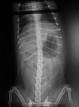

Добрый день! Чтобы убедиться, что у собаки копростаз(запор), сделайте рентген.снимок брюшной полости и разместите на форуме. Учитывая возраст собаки, необходимо провести полное обследование, включающее в себя анализы крови ОКА и БХ, УЗИ брюшной полости..

наконец то сделали снимки с таким трудом...посмотрите пожалуйста !!! собака все такая же, в туалет никак...таблетками ее накормить большая проблема...может что в уколах ???